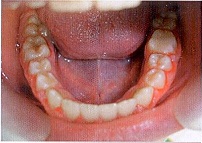

Осмотр полости рта (Рис. 2):

Рис. 2

St. localis: гематома слизистой верхней губы, отек и гиперемия слизистой в области верхних резцов, гематома в области зубов 2.2, 2.3, обратное резцовое перекрытие в области 1.1, 2.1, 2.2. Экструзия зубов 1.1, 2.1 и 2.2, подвижность зубов 1.1, 2.1 и 2.2 II степени (Рис. 3).

Рис. 3